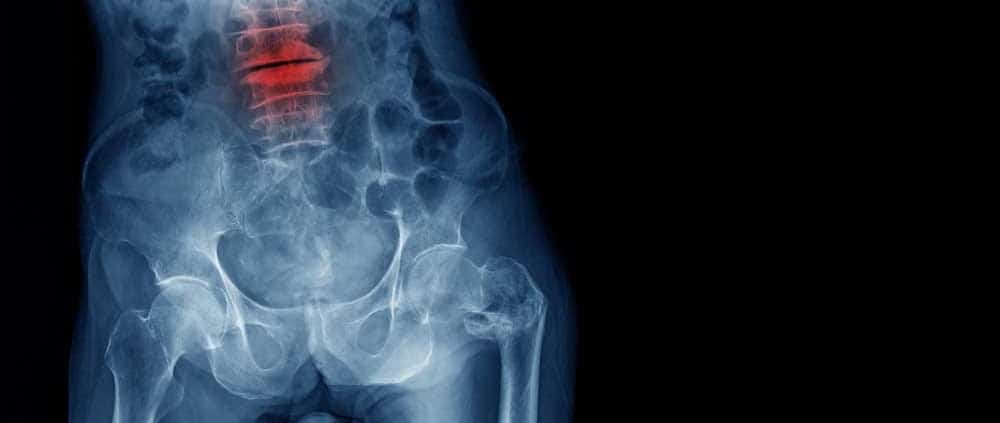

Wat is een inzakkingsfractuur van de wervelkolom?

Een inzakkingsfractuur van de wervelkolom of een compressie fractuur wil zeggen dat u een breuk in de wervel heeft. Hierdoor zakken één of meerdere wervels in. U kunt zo een stabiele of instabiele fractuur hebben. Afhankelijk van welke van de twee u last heeft, kan een behandeling worden ingezet.

De meest voorkomende oorzaak is een osteoporose, ook wel bot ontkalking genoemd. Dit kan ontstaan door ouderdom, hormonen, overgangsklachten en vitamine D gebrek. Ook kan het ontstaat door een ongeluk (trauma) of door een tumor. Een van de klachten die ontstaat bij een inzakkingsfractuur is heftige pijn in de rug. Soms voelt de pijn dof en soms enorm scherp. De pijn wordt alleen maar erger bij veel bewegen.

Daarnaast kunnen er ook standsveranderingen van het lichaam plaatsvinden. U kunt bijvoorbeeld meer met een bolle rug gaan staan of uw lichaamslengte wordt kleiner. Dat komt doordat de wervel is ingezakt. Daardoor kunt u ook last krijgen van ademhalingsproblemen.